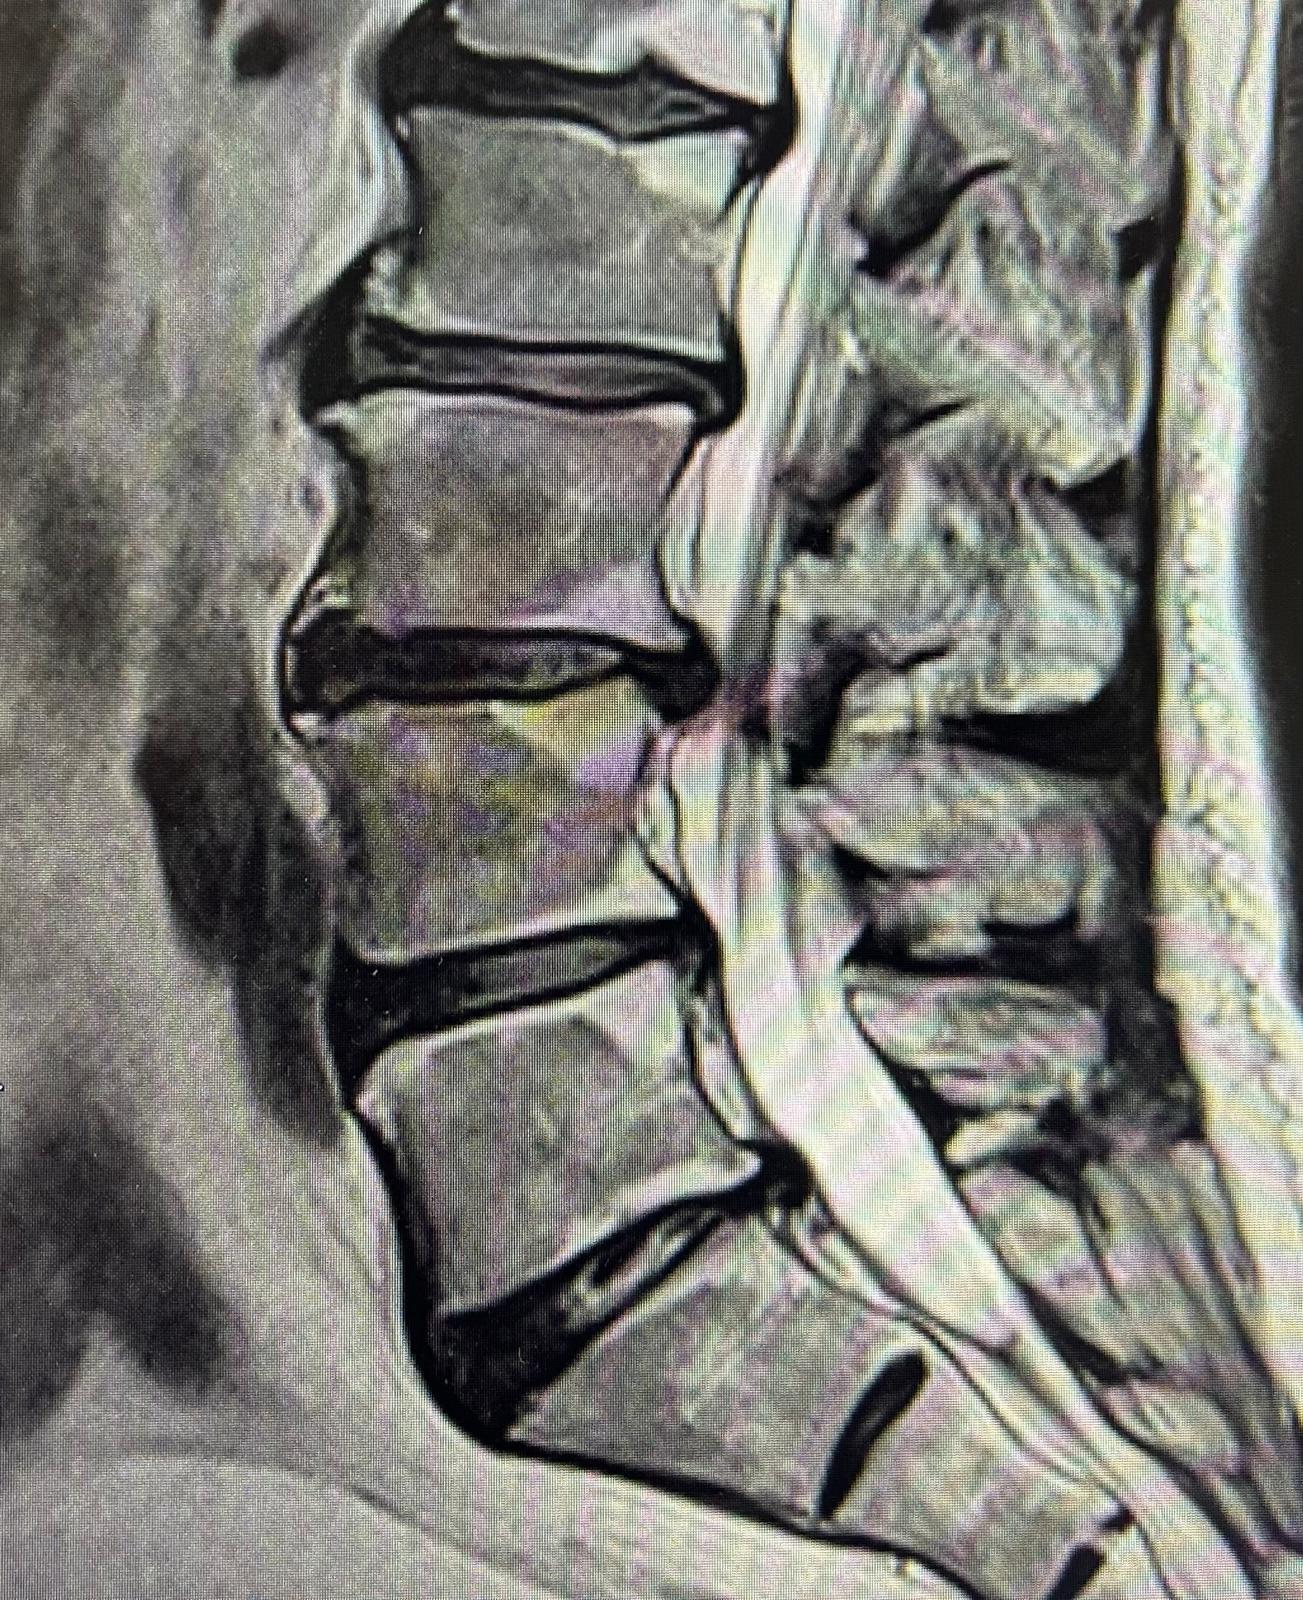

- Dyskopatie szyjne i lędźwiowe

- Choroba zwyrodnieniowa kręgosłupa ze stenozą kanału kręgowego